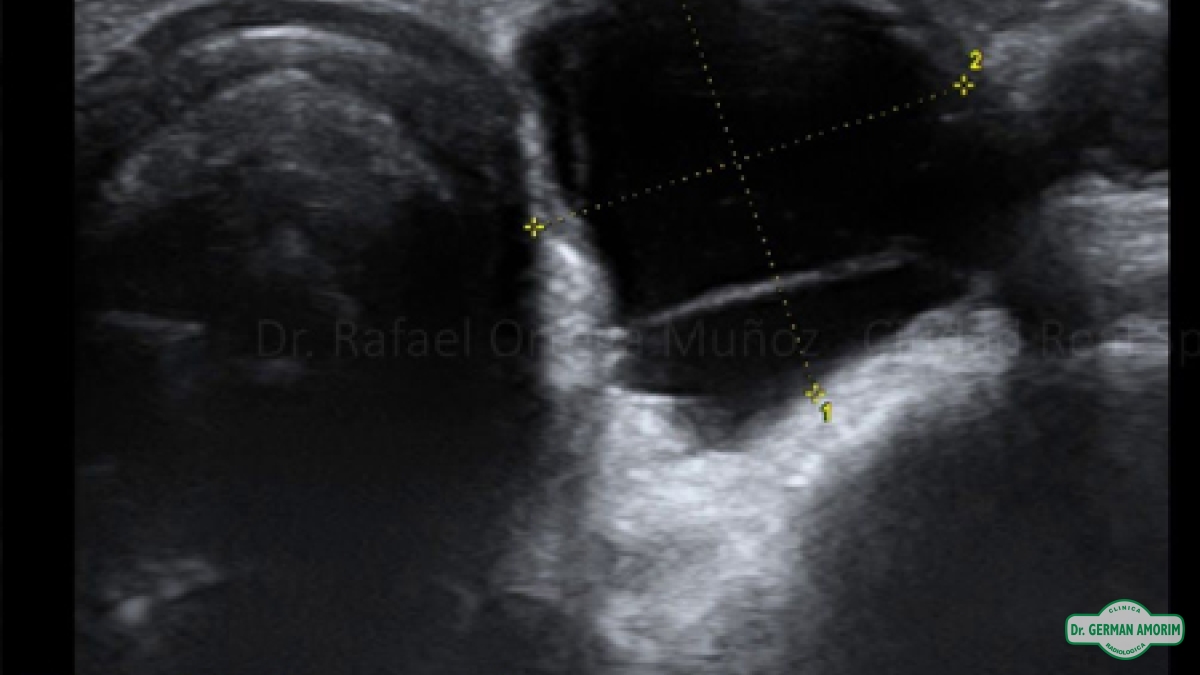

Las imágenes por ultrasonido es un examen médico no invasivo que ayuda a los médicos a diagnosticar y tratar condiciones médicas. El ultrasonido de tiroides produce imágenes de la glándula tiroides y estructuras adyacentes en el cuello. La glándula tiroides se ubica en la parte delantera del cuello, justo por encima del hueso de la clavícula, y tiene forma de mariposa, con un lóbulo a cada lado del cuello conectados por una banda estrecha de tejido. Es una de las nueve glándulas endocrinas ubicadas en el cuerpo que producen y envían hormonas al torrente sanguíneo.

La glándula tiroides produce la hormona tiroidea que ayuda a regular una variedad de funciones corporales, incluyendo la velocidad de latido de su corazón. Es muy común que en sus tiroides se desarrollen áreas irregulares o nódulos que pueden, o no, ser evidentes en la superficie de la piel. Aproximadamente entre el cinco al 10 porciento de los adultos tienen nódulos tiroideos, a veces palpables otras sólo localizados por ecografía.